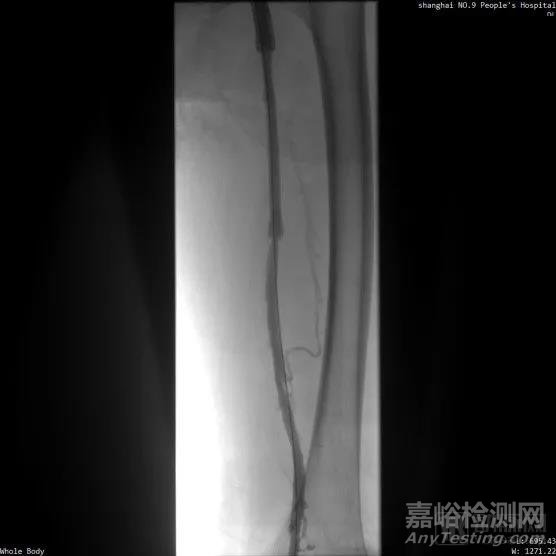

■ LuVoCaptor取栓前后管腔造影對照:

取栓術前管腔造影

取栓術后管腔造影